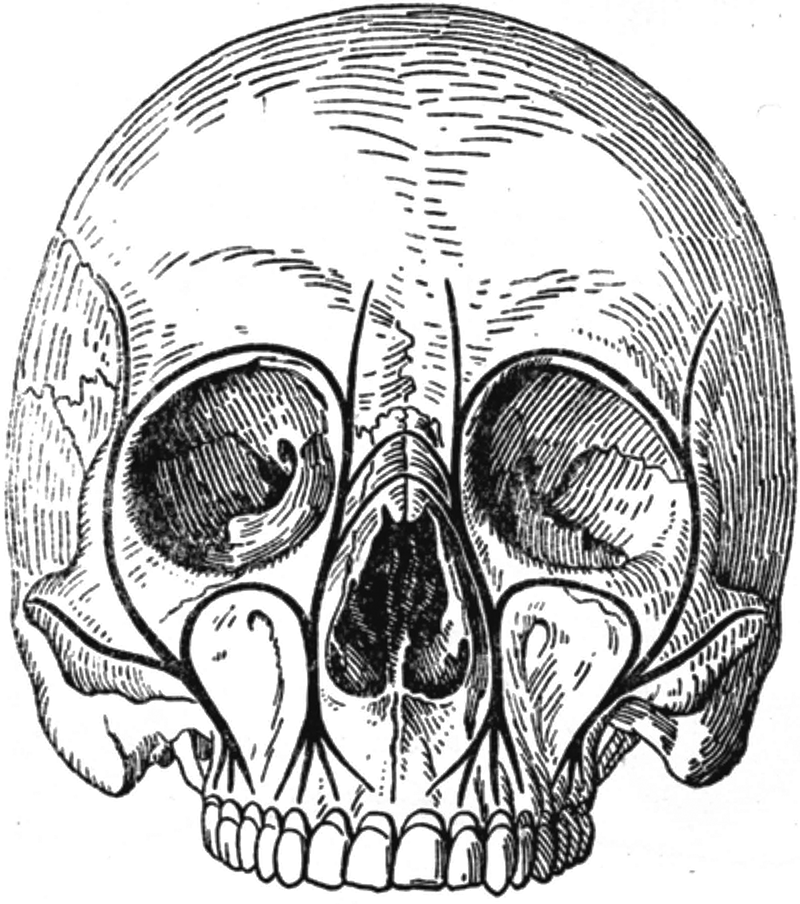

Chapter 8. Anatomical and functional peculiarities of the maxillofacial area and neck

The human face begins its growth during the fourth week of intrauterine life with the development of the branchial apparatus. A 1-month-old embryo has no real face but the key primordia have already begun to gather.

The oral cavity of the embryo is bounded by the frontonasal process and by the maxillary and mandibular processes of the first branchial arch.